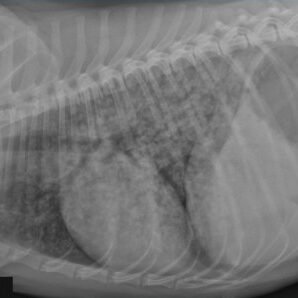

Lung (pulmonary) dysfunction can be presented for shortness of breath, exercise intolerance and having difficulty breathing. 🫁🩻 Pulmonary abnormalities can occur secondary to the effects of the leptospiral toxin on lung tissue, and from fluid exudation secondary to vasculitis.